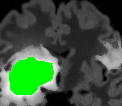

In Fig. 12, we show several tumor segmentation results for all data types.

In Table II, we compare results obtained using different descriptor structures:

patch-based [48], superpixel-based [54],

and superpatch-based (= pixels).

We use the Dice coefficient [55] as evaluation metric,

measuring the overlap between the automatically segmented structure and the ground truth.

The superpixel-based approach

appears very limited since it fails at capturing the tumor context and their location in other images.

Regular patches are also limited in this context, due to the variations in the structure shapes.

Superpatches provide a robust descriptor, since they follow image intensities and capture the superpixel neighborhood,

leading to more accurate segmentation.

These experiments demonstrate that superpatches within the SPM framework provide fast and accurate segmentation results

even on non-registered multi-modal images with poor resolution.